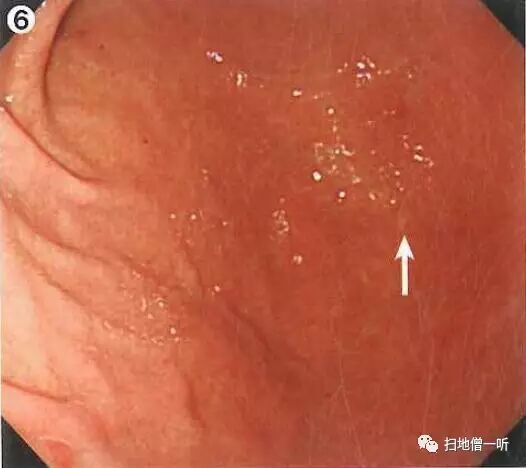

A:胃癌在图6。HP感染胃癌。

背景粘膜为C-2型萎缩。体部淡红色弥漫发红提示HP感染。体下部大弯侧可见小片褪色斑,周围未见相同表现病灶。

接近观察可见褪色斑边界较清晰